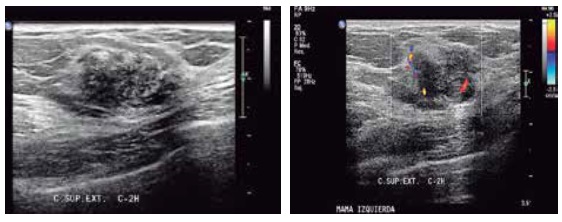

Características radiológicas en ecografía

En la investigación bibliográfica de las características de imagen en CMTN, se ha encontrado que en la ecografía la mayoría de las lesiones se manifiestan como nódulos o masas hipoecoicas solitarias, con contornos lobulados o mal definidos, y ocasionalmente presentan sombra acústica.

Además, otras investigaciones similares respaldan estos hallazgos. Se encontró que en un alto porcentaje de casos (hasta el 92%) el CMTN se presentó como nódulos, y en un 7,2% de los casos se manifestó como otra lesión. La gran mayoría de estos nódulos presentaron características hipoecoicas, con una forma ovalada predominante (49,2%). En cuanto a los márgenes, la mayoría de los nódulos tenían márgenes microlobulados (39,7%), y solo un 4% presentaron márgenes espiculados.

Al analizar los hallazgos acústicos posteriores, el refuerzo acústico posterior se destacó como uno de los hallazgos más relevantes, con un 35,5% de los casos. También es común observar que la vascularización de estas lesiones tiende a ser de predominio periférico o ausente. Sin embargo, en un pequeño porcentaje (5%) de los casos, las lesiones pueden pasar desapercibidas en los estudios de ultrasonido.(5, 19, 22, 23, 24, 25, 26, 27)

Características ecográficas del CMTN

Los resultados de las características ecográficas revelan los siguientes hallazgos en la investigación. Se describe la forma del nódulo de la siguiente manera: en su mayoría es ovalado (n = 13,76%), con márgenes microlobulados (n = 7, lo que corresponde al 41%), seguido de márgenes circunscritos (n = 5, equivalente al 29%). Además, se observa que son hipoecoicos (n = 16, lo que corresponde al 94,2%) y se ubican de manera paralela al eje cutáneo (n = 15, equivalente al 88,2%).

En relación con los hallazgos acústicos posteriores, se destaca que 14 pacientes, que conforman el 82% del grupo, no presentaban hallazgos acústicos ni calcificaciones intra ni extra nodulares.

En cuanto a la vascularización, se observa que en 14 pacientes (equivalente al 82%) no se detectó vascularización en el estudio realizado con Power Doppler. En contraste, 3 pacientes presentaban vascularización periférica, representando el 17,6% de la muestra. En ninguno de los casos se informó distorsión arquitectural ni cambios cutáneos. Sin embargo, en 15 pacientes se observaron adenopatías axilares, lo que corresponde al 88,2% del grupo estudiado.

Anexo 2. Imágenes ecográficas del CMTN